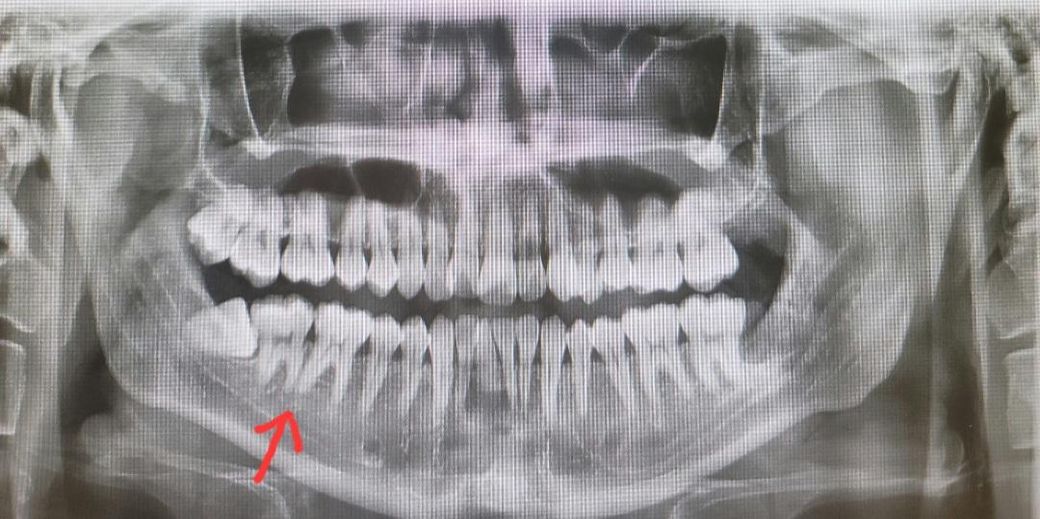

엑스레이 사진에 표시한 치아와 치아 사이를 혀로 갖다대고 움직여 보면 약한 시림 증상이 있습니다

(오른쪽 사랑니 바로 앞 어금니와 그 다음 어금니 사이)

시린 느낌은 사랑니 바로 앞에 있는 치아에서 나오는거 같긴 한데 너무 애매해서 정확히 판단을 못하겠습니다

사랑니가 그 앞 어금니에 치근흡수, 충치 유발해서 지금 그런 증상이 있을 확률이 높습니다.